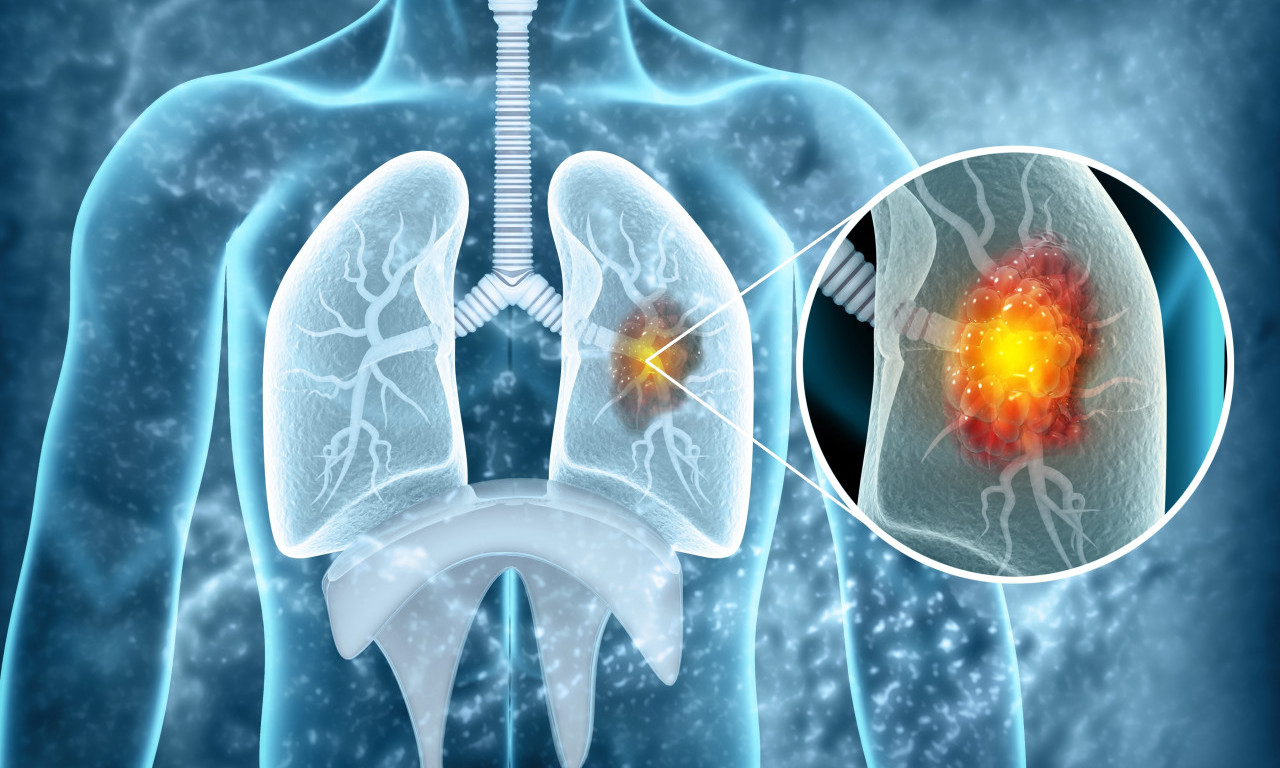

rak pluća

VEŠTAČKA INTELIGENCIJA OTKRIVA RAK PLUĆA MESEC DANA UNAPRED! Potrebno je uraditi osnovne medicinske analize

Na svaka dva sata u Srbiji jedna osoba premine od KARCINOMA PLUĆA! Od jeseni počinje "borba" u SRBIJI, a evo i kako

Svetski dan borbe protiv raka pluća obeležava se svake godine 1. avgusta.

Rak pluća je vodeći uzrok smrti od raka u svetu, a godišnje ima 1,8 miliona smrtnih slučajeva od kancera pluća

ALARMANTNI PODACI U SRBIJI! Od RAKA PLUĆA oboli 7.000 SRBA godišnje, što nas stavlja na drugo mesto u Evropi

CRNA STATISTIKA: 70% obolelih RAK PLUĆA otkrije tek kad su ŠANSE ZA IZLEČENJE MINIMALNE, ovo je NAJVEĆI PROBLEM

Srbija drži PRVO MESTO u Evropi po smrtnosti od KARCINOMA PLUĆA - zašto je to tako?

Ukoliko se otkrije na vreme, ova opaka bolest je izlečiva